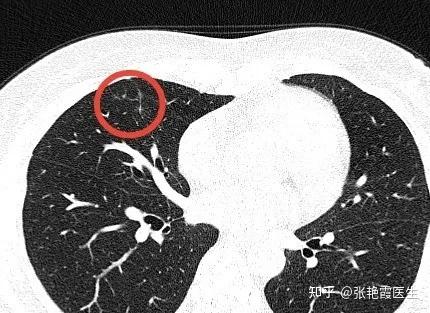

查出肺结节也不可怕,90%以上都是良性 - 抖音

如何辨别肺结节是良性还是恶性?主要看三点